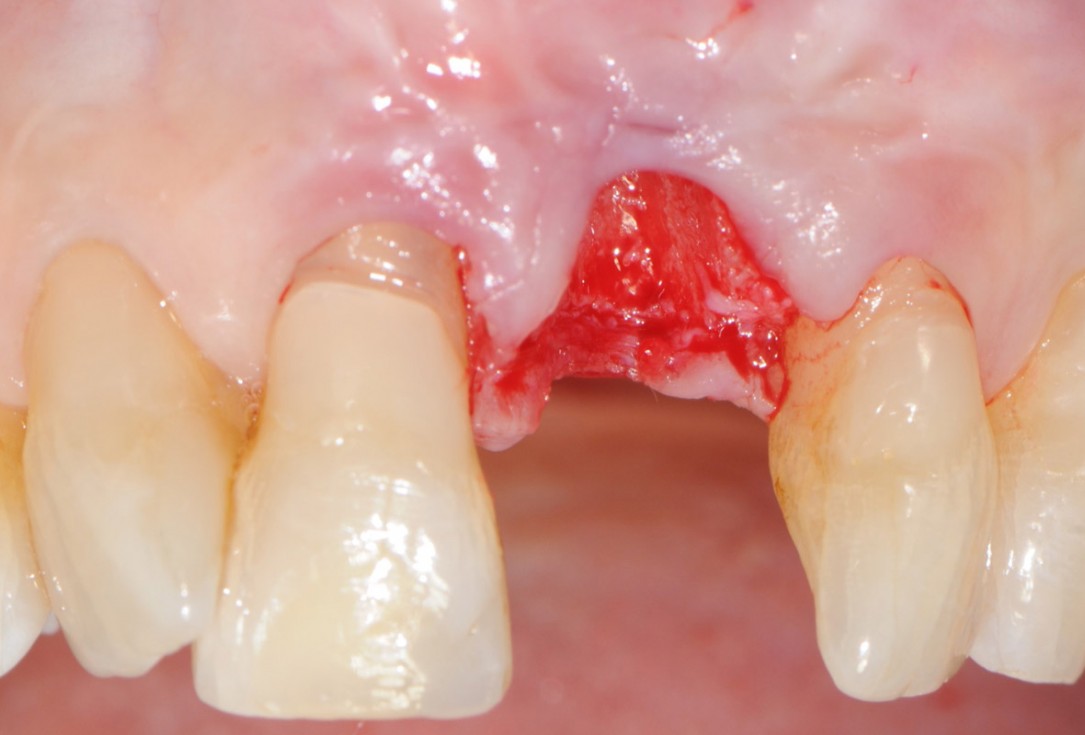

5/18 - After atraumatic extractionTooth extraction and socket sealing with mucoderm® - Dr. A. Rossi